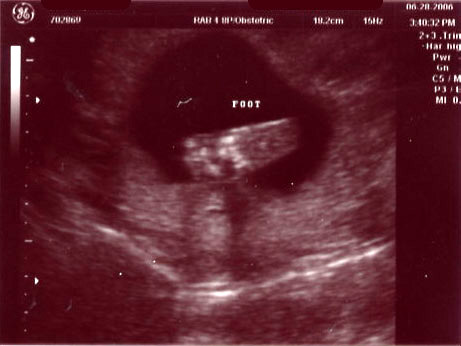

| June 28, 2006 - Twenty Week Ultrasound: IT'S A BOY!!! |

Today was probably the

longest day of my life having to wait for our 3:00pm appointment. I

went to work today, but didn't get much done since I was so excited to

finally find out what we were having. We got to the doctor's and they

took us right away. Within 44 seconds of the technician turning on the

ultrasound machine, she showed us the picture of the legs spread wide open

and it was obvious that we were having a boy!! He was so active

throughout the entire ultrasound, kicking and turning all over the place.

He is absolutely beautiful!!! I am in love with him already. He

weighed 13.5 ounces and he is perfect and healthy!! We are so excited

to start planning the nursery for our little man. Here are the

ultrasound pics from today. Enjoy!! ~Jen

Baby foot |